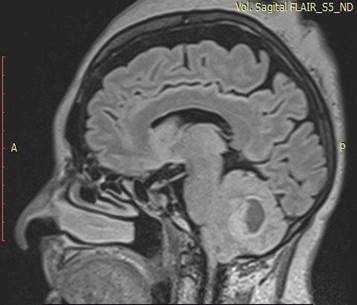

A ressonância magnética de crânio evidenciou grande lesão sólido-cística no corpo medular do cerebelo à direita, com efeito expansivo significativo (Figura 1).

A lesão, com dimensões 30,9x32,0x36,4, apresentou hipersinal em T2 (Figura 2) e FLAIR (Figura 3), hipossinal em T2, depósitos de hemossiderina nas bordas, área de restrição à difusão e intenso realce pós-contraste na porção sólida. As áreas císticas sugerem alto grau de necrose.

Figura 3. Sagital FLAIR